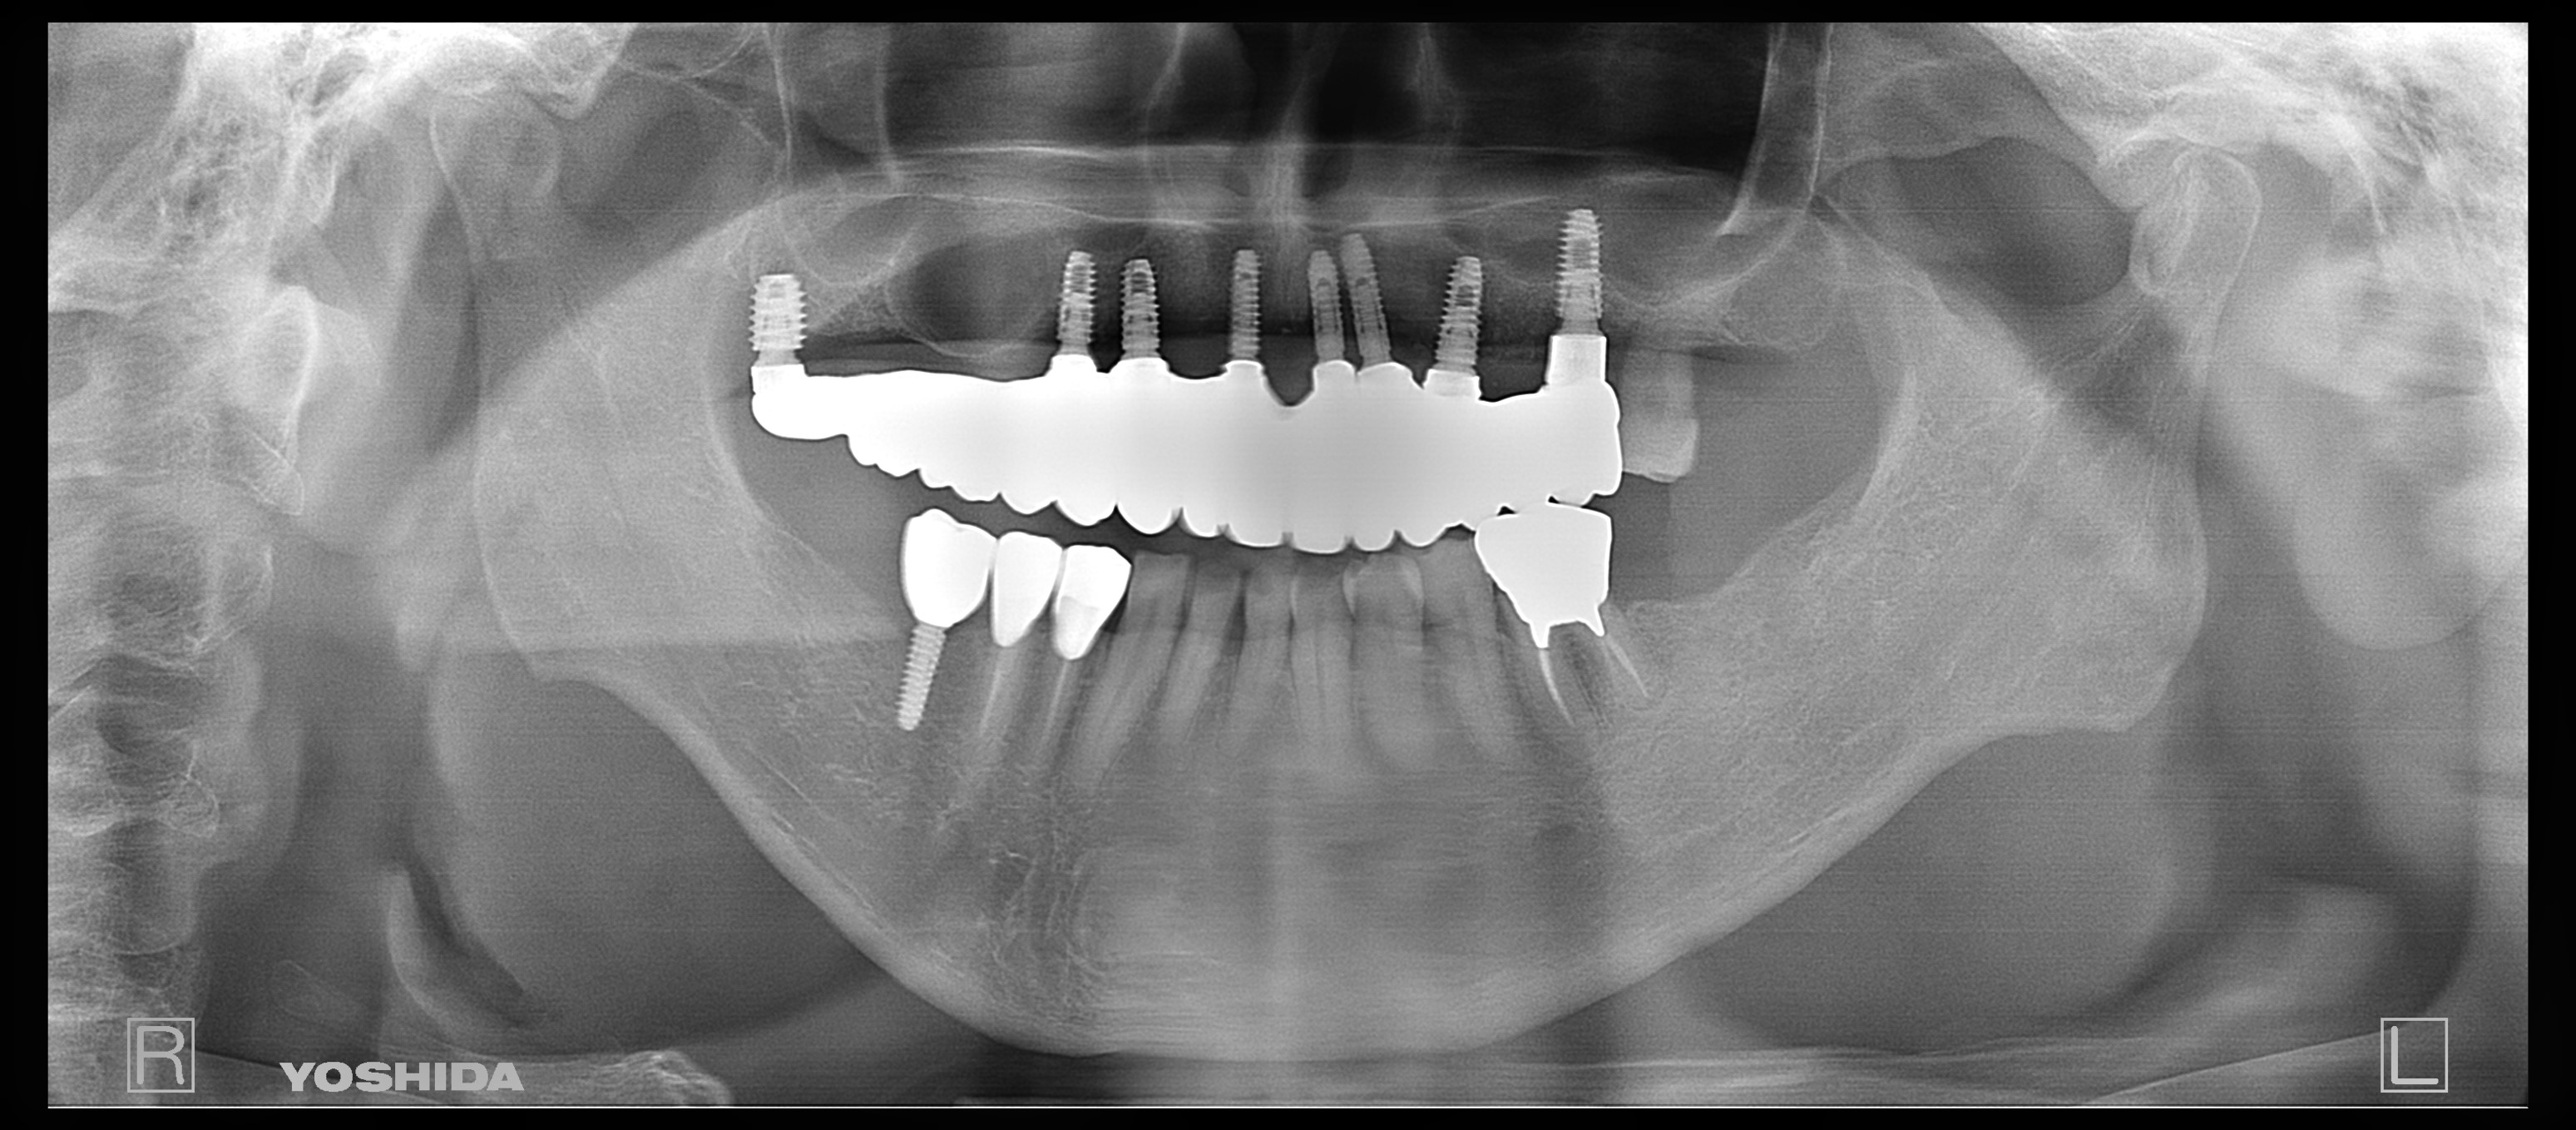

左側のレントゲンがが最初の状態です。右側がインプラントを入れ、被せ物まで入れた状態のレントゲンです。